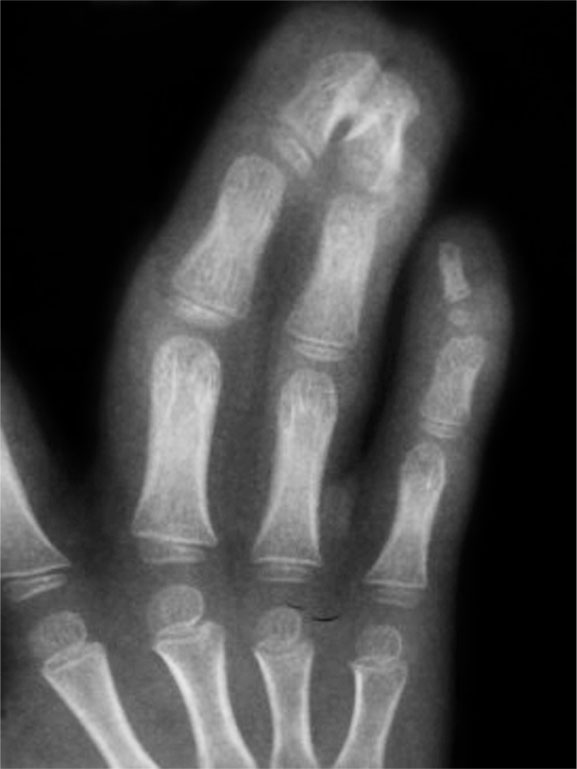

图1-2-29 指间关节融合

图1-2-30 指间关节融合X 线片

先天性双手指间、掌指关节纤维性(或软骨融合)融合